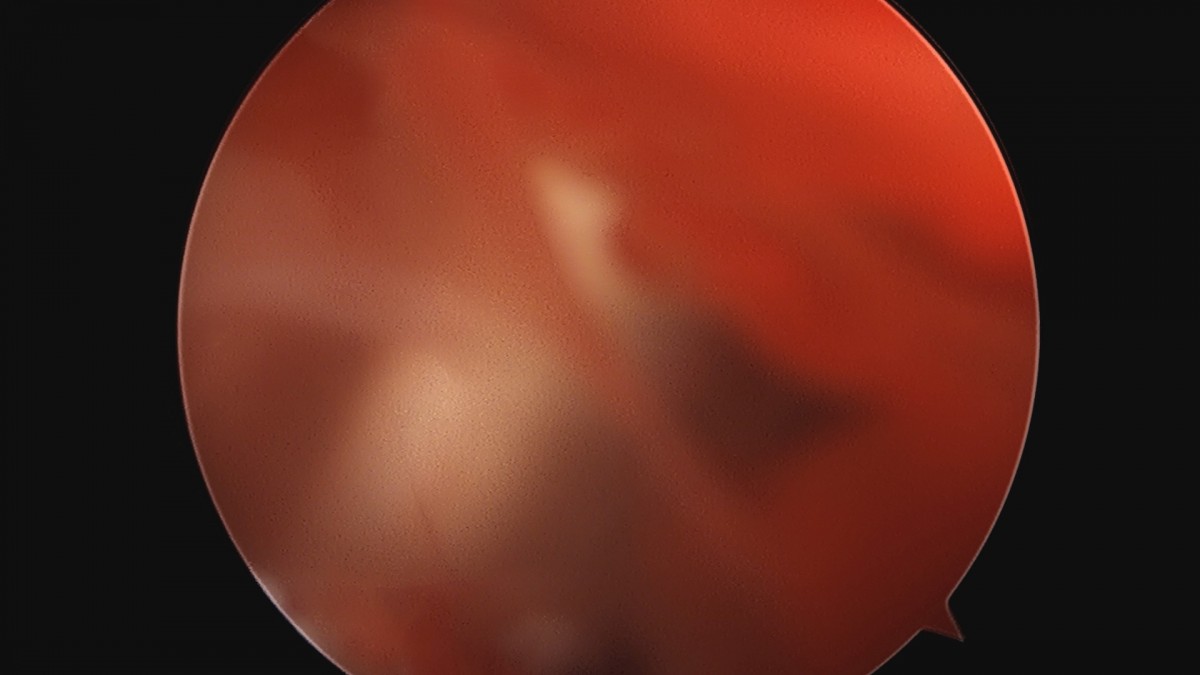

이재상원장님 어깨 견봉하 감압술 김선O 환자

dae765e4d9ac96aee867c9d6292d8784_1758004048_3083.jpg